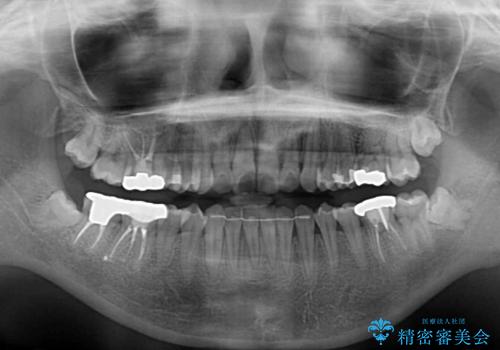

- 上下歯列全体のデコボコを気にして来院された患者様です。

主に下顎歯列全体の後方移動とIPR(歯と歯の間を削る)によってデコボコが解消するように設計し、インビザラインにより治療を行うこととしました。

1年半程度で終了するのではないかと予想しましたが、途中1年以上の来院がなく、トータルで3年の時間がかかってしまいました。

前歯のデコボコはより改善することが望ましい状態でしたが、患者様の希望により終了することとなりました。